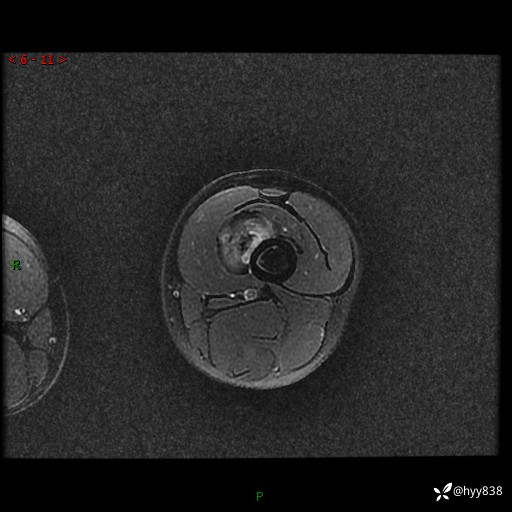

左大腿MRI平扫+增强